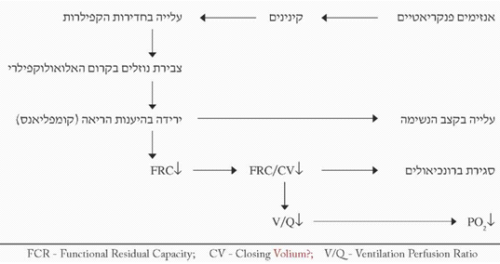

ריאות - היפוקסמיה מתפתחת בכ-40% מהחולים בדלקת הלבלב, 20% יפתחו תסמונת המצוקה הנשימתית של המבוגר (ARDS) וב-20% יימצא תפליט פלאורלי המאופיין ברמות דיאסטאז גבוהות. ההיפוקסמיה מקורה בדלף המתפתח בריאות. הדלף נובע מפעילות אנזימי הלבלב על הקינינים ושפעולם. אלה גורמים לעלייה בחדירות הנימיות (Capillaries) ולצבירת נוזלים בקרום בין הנאדיות והנימיות (Alveolocapillary membrane). כשכמות הנוזל בקרום גוברת על יכולתה של המערכת הלימפתית לסלקו, מצטבר הנוזל בקרום וגורם לכמה שינויים בתפקוד הריאות. ירידה בהיענות הריאה (Compliance), גורמת לעלייה בעבודת הנשימה, לירידה ב-FRC (Functional residual capacity) ולעלייה ב-CV (Closing volume), הגורמות לסגירת הברונכיאולים ולחוסר אוורור חלק מהריאה. חוסר אוורור זה משנה את היחס החשוב שבין הזילוח לאוורור, וכך בחלק מהדם הגזים אינם משוחלפים ולכן לחץ החמצן (PO2) בדם העורקי יורד, ומתפתחת היפוקסיה.

צבירת הנוזלים החודרים לתוך הנאדיות (Alveoli) גורמת לשטיפה של החומר פעיל השטח (Surfactant) מעל פני האלוואולי, לעליית מתח הפנים בהם, ולפיכך לתמט של הנאדיות הקטנות ולחוסר אוורור שלהם. אלה יגרמו החמרה ביחס האוורור לזרימה - V/Q, הגברת הדלף והיפוקסיה. הפגיעה ביצירת הסורפקטנט עלולה להיות גם ישירה על-ידי פגיעה מטבולית, כגון בהרעלת חמצן (תרשים 3.9).

הבצקת בתאי האנדותל, ירידת הנפח הריאתי עקב הירידה בהיענות הריאתית ומיקרו-תסחיפים, כל אלה גורמים לעלייה בתנגודת כלי הדם, ולכן להפרעות בזילוח או ליתר דיוק בחלוקת הדם בין האלוואולי השונים, וכך האלוואולי המקבל את מרבית האוויר לא יהיה בהכרח גם זה המקבל את מרבית הדם. התוצאה היא החמרה בדלף ועלייה בלחץ של העורק הריאתי, המכריחה את הלב הימני להתכווץ חזק יותר, כנגד התנגדות גבוהה יותר. אולם הוא מתקשה לעמוד במשימה עקב הפרשת הפפטיד המדכא את פעולת שריר הלב (MDF) וכך גורם לכישלון הלב הימני. העלייה בעבודת הנשימה, הנגרמת עקב הסיבות שנמנו, מלווה בהיפוקסיה וגורמת לחמצת מטבולית.